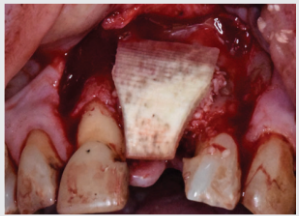

The patient presented with a poorly healed site with previously failed dental implants. An aggressive guided bone regeneration procedure was indicated, using a combination of DALI Grafts, including, DALI Amnion Chorion Membranes, to facilitate bone growth for future implant placement.